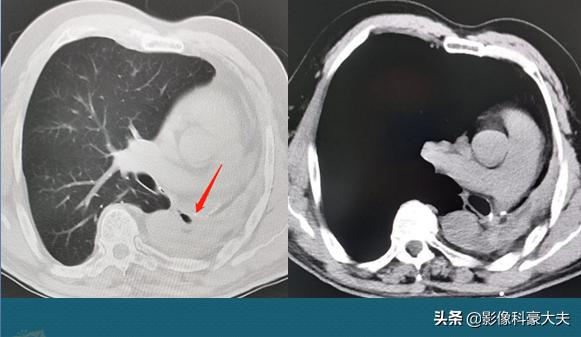

3.小细胞肺癌,放化疗6年后复发

这位女病人值得被评为今年的抗癌幸运星!她在2009年因为咳嗽、痰中带血,查出右侧小细胞肺癌,经过放化疗为主的综合治疗后肿瘤萎缩消失,很幸运!6年后(2015年)查出复发,再一次放化疗,肿瘤再次萎缩,半个月前复查,恢复很好:

小细胞肺癌复发率高,一旦复发,癌细胞常常对治疗很抗拒,像这位女士这么幸运的病例不多,这方面还需要更多深刻的研究,找到癌细胞复发的开关并关闭它。